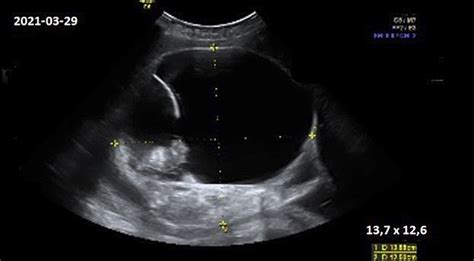

| 4-5 savaitė | 1 000 - 50 000 | Matomas vaisiaus maišelis ultragarse; testas itin tikslus. |

Ne visada. Padidėjęs hCG gali būti susijęs su daugiavaisiu nėštumu, bet taip pat su kitomis fiziologinėmis būklėmis ar laboratoriniais skirtumais. Diagnozei patvirtinti būtinas ultragarsas.